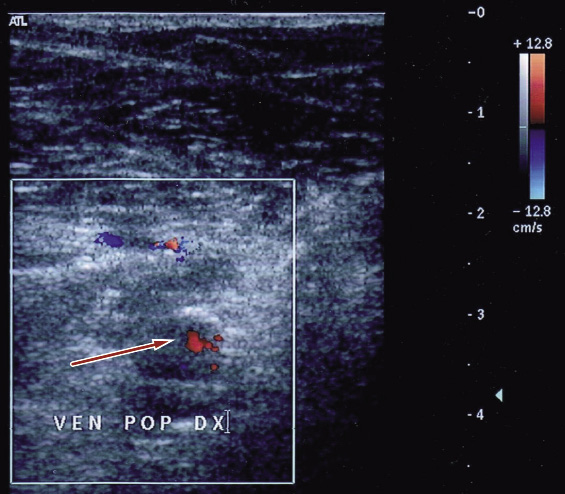

Un controllo EcoDoppler a giugno 2013 dimostra la cross safeno-femorale destra pervia, trombosi parzialmente ricanalizzata della vena poplitea e della femorale superficiale fino al terzo superiore della coscia (Figura 4).

Figura 4. Ecografia-Doppler venosa dell’arto inferiore destro effettuata a giugno 2013 (vena poplitea destra)